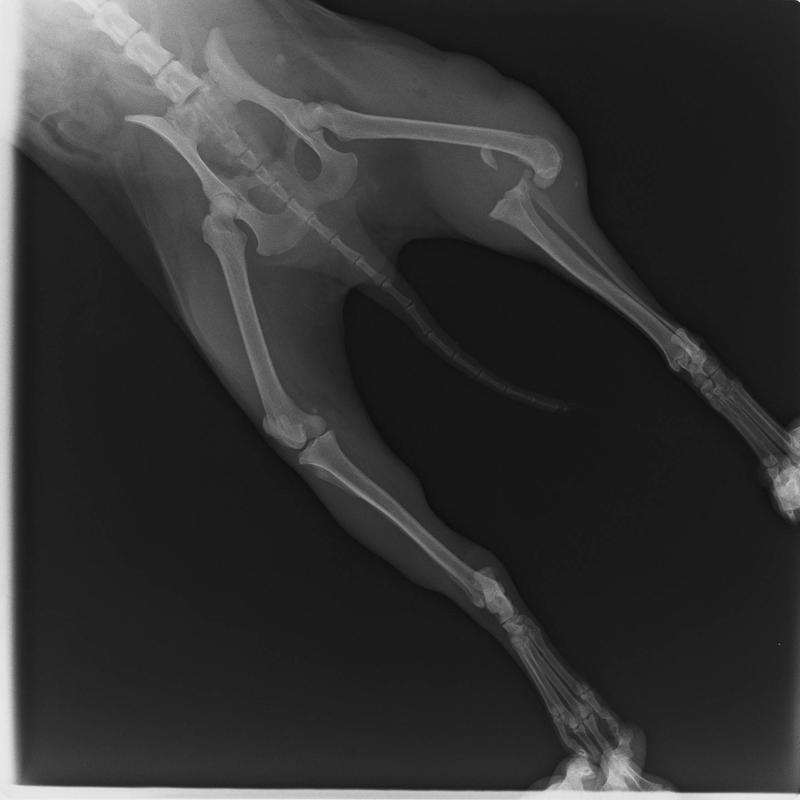

これが術前の写真です。前回のと比べて明らかに膝の関節が上下でずれてるのがわかります。

脱臼して靱帯も完全に切れており、もはやブラブラ。